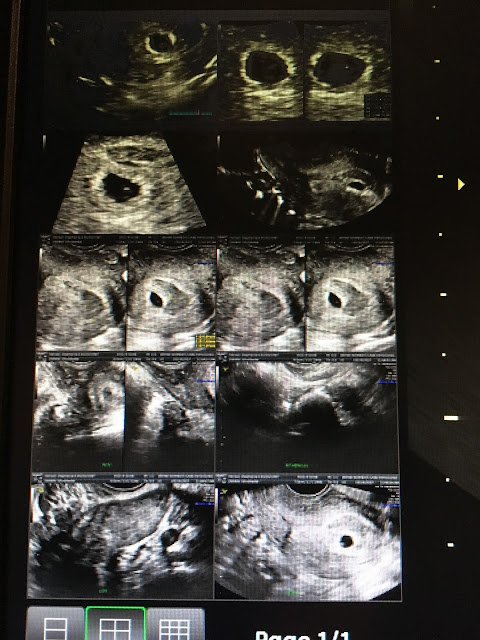

That afternoon the nurse called with my Hcg results 3849, Progesterone 47. Ultrasound showed a Gestational Sac, and a Yolk Sac but no fetal pole yet. We were still just a little too early at roughly 5 weeks 2 days. Dr. Maud still wanted me to come to Omaha the following Monday to check in with them, so we took the weekend easy and tried to not get my hopes up of seeing a little baby come the next ultrasound.

| Gestational sac, yolk sac in the inside |